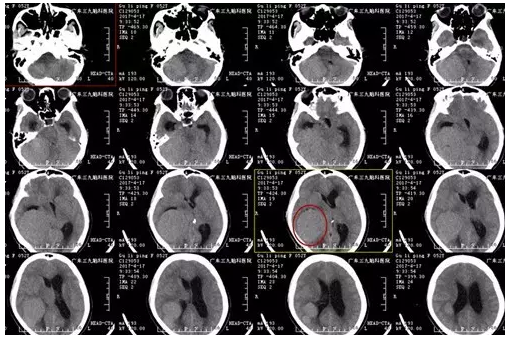

古女士,52岁,头痛1年,遂渐出现恶心、呕吐、四肢乏力5天,外院CT检查结果提示右侧天幕巨大占位性病变,为求进一步,有效治疗,来我院就诊。

图1:术前CT显示右侧中后颅窝团片状等、稍高密度影

患者由神经外一科接诊,入院后完善相关检查,术前CTA显示中后颅窝占位病变内多发血管影,MR显示肿瘤大小约66mm×58mm×73mm,完善术前检查后,行全麻下右侧颞枕部-右侧后颅窝巨大占位性病变切除术+ICP探头置入术,手术由神经外一科主任张良主刀完成,术程顺利,术后恢复良好,未见并发症。